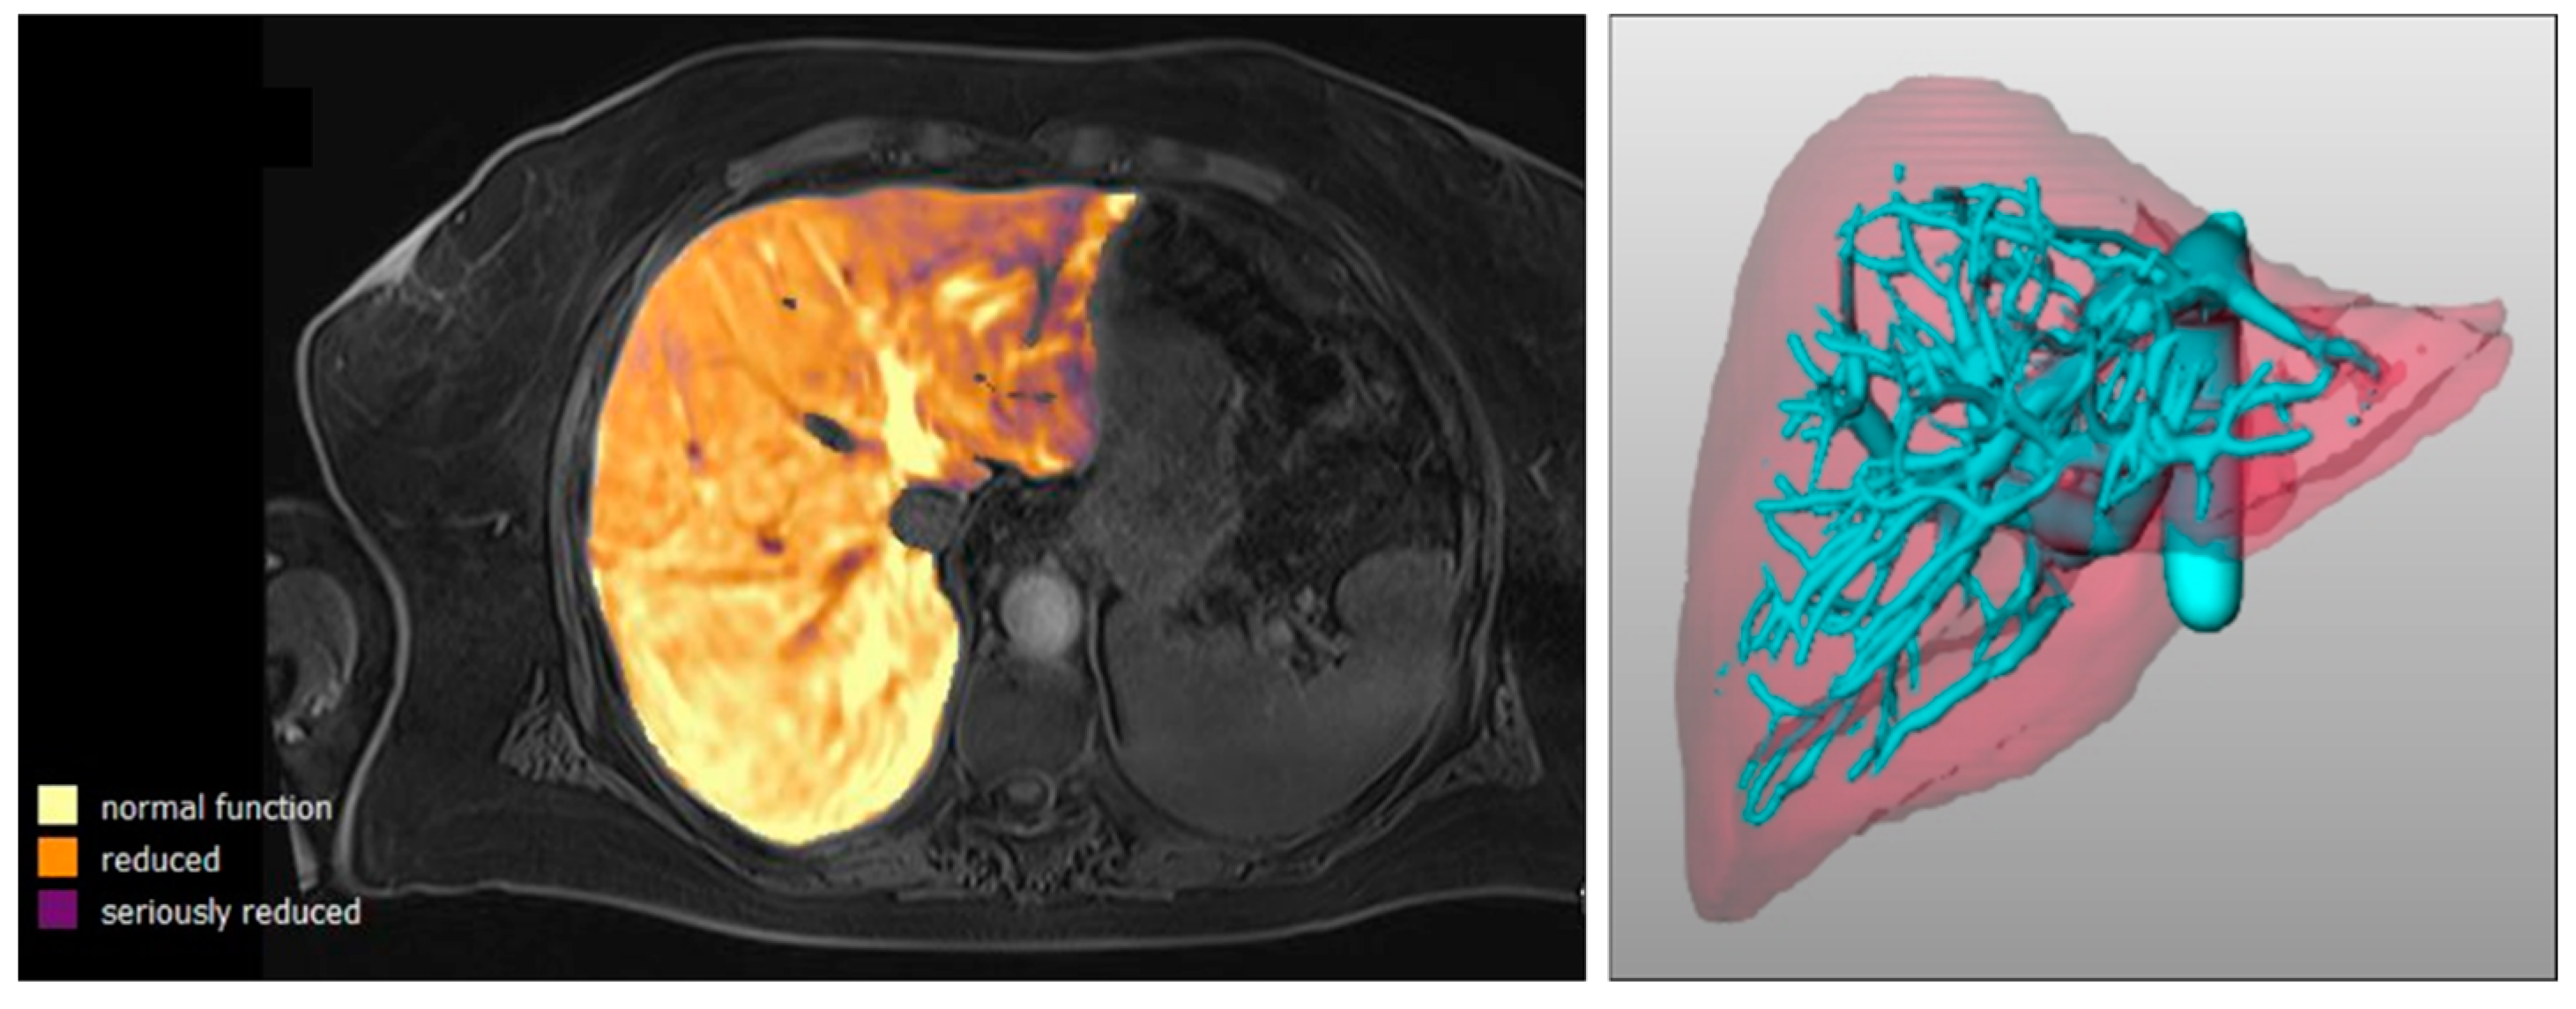

2.2. Image Acquisition and Analysis